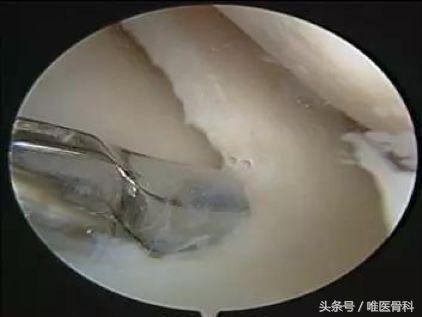

因为半月板的很大一部分是没有血液供应的,有比较高的概率无法自行愈合,这个时候就需要手术干预。现在半月板的手术都是通过关节镜进行治疗的,这是一种微创的治疗方式,通常只需要两个1cm左右的切口就可以完成。根据半月板损伤的类型和程度,可采取半月板成形术或者半月板缝合术进行治疗。

半月板缝合术